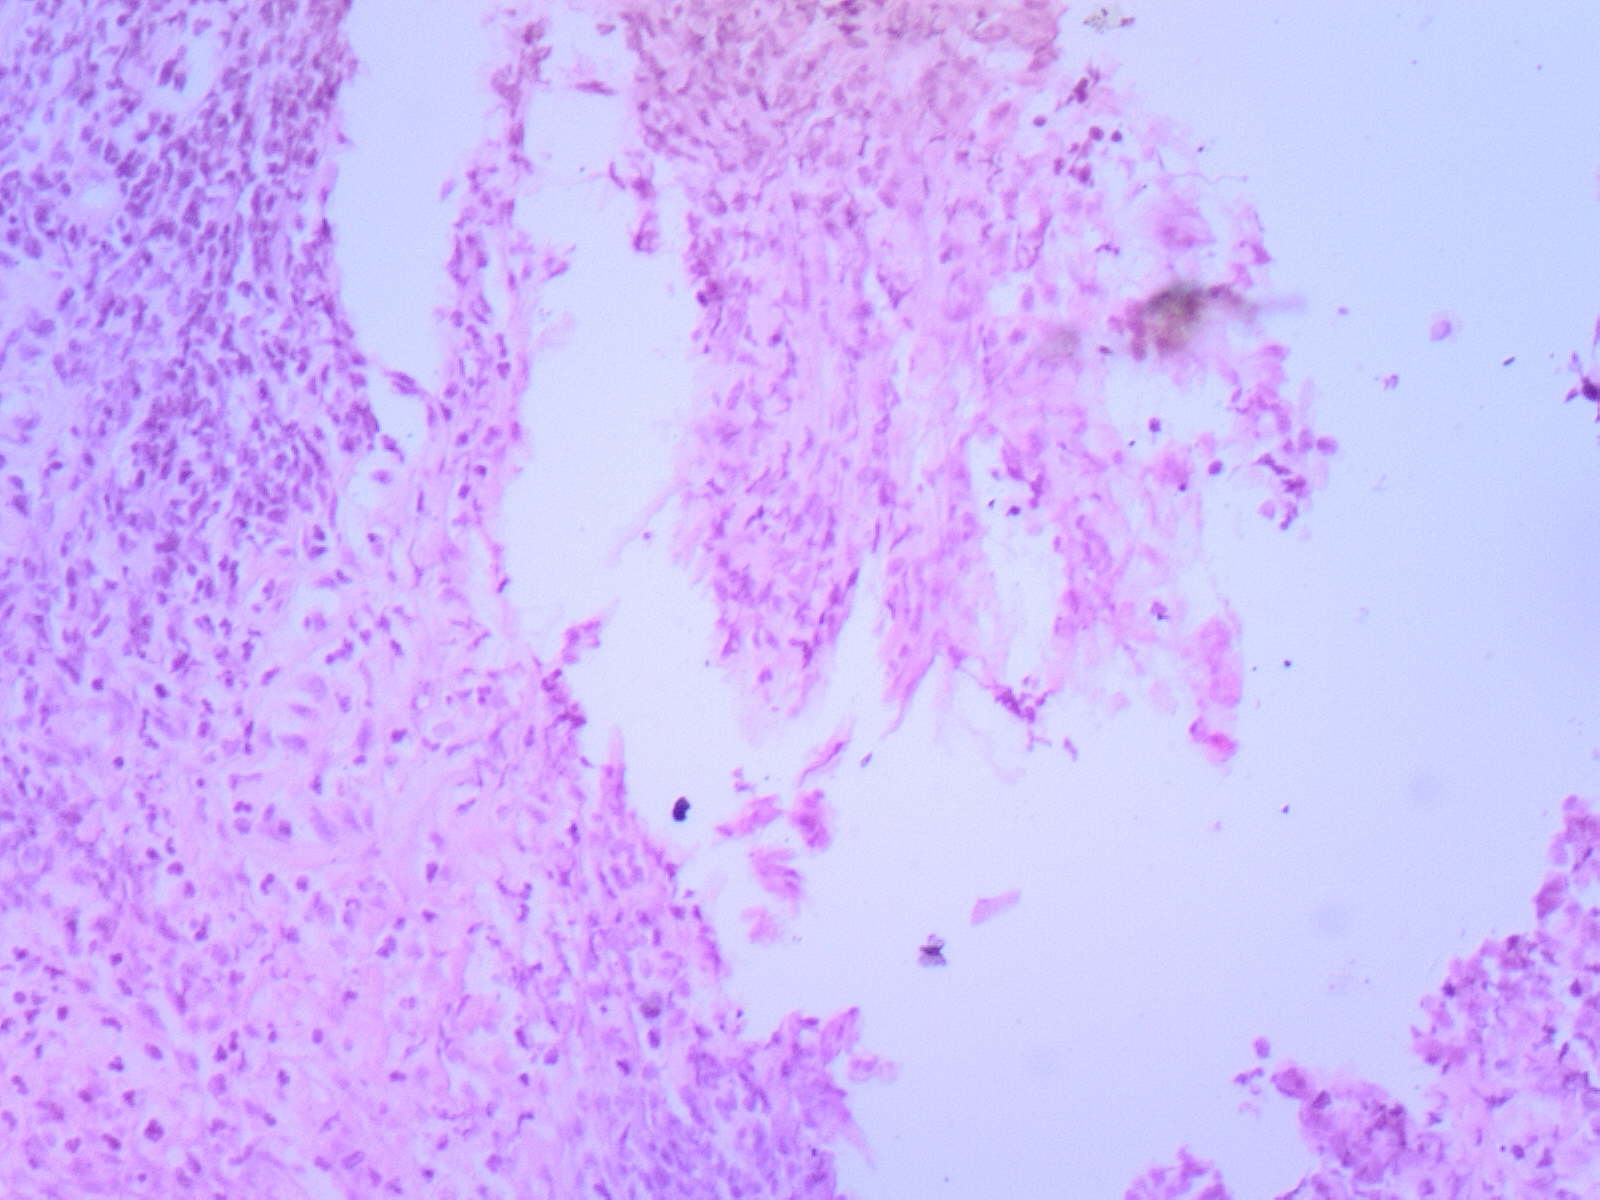

200. Хроническая язва желудка в период обострения Визуально в стенке желудка определяется язвенный дефект. На малом увеличении в дне язвы отмечается широкая зона фибри­ноидного некроза с воспалительной клеточной инфильтрацией. За зоной некроза располагается слой грануляционной ткани с боль­шим количеством сосудов. Самый глубокий слой представлен пучками и тяжами зрелой соединительной ткани с участками гиалиноза. Встречаются сосуды с резко утолщенными стенками и разросшиеся нервные волокна по типу невром.

Существенные элементы: 1. гнойно-некротический слой

2. слой грануляционной ткани

3. слой зрелой соединительной ткани

4. склерозированные стенки сосудов

5. разросшиеся нервные волокна